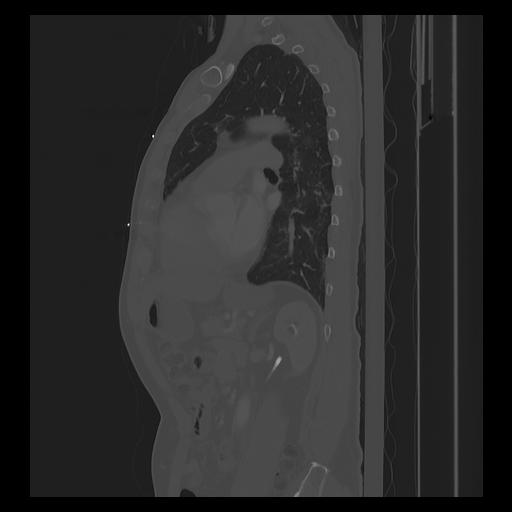

33 PULMON,CE,Sagittal,3.000,PULMON,Sagittal,